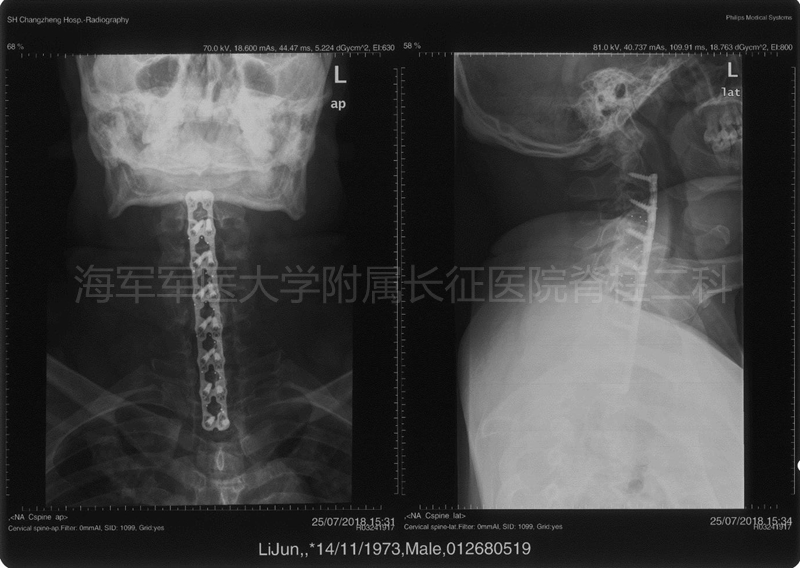

术后侧位平片矢状位MRI和矢状位、水平位CT

术后平片